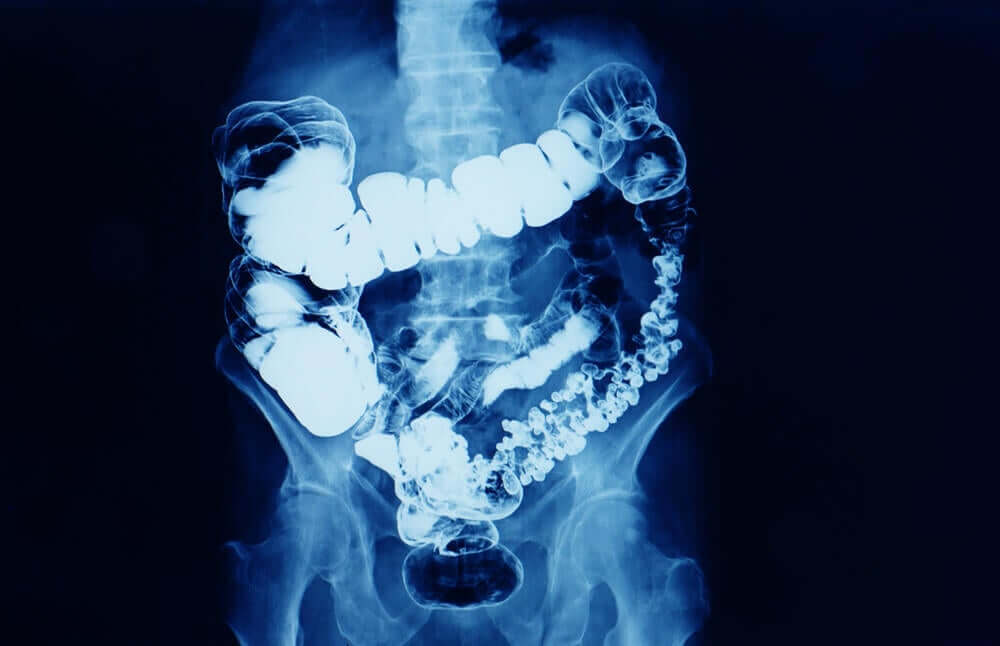

Verdensdagen for tyktarmskræft mindes den onkologiske sygdom, der udvikler sig i tyk- og endetarmen. Udtrykket kolorektal cancer er også en måde til at henvise til dette sted.

Tyktarmen og endetarmen er den sidste del af fordøjelseskanalen efter tyndtarmen. Det er her, afføringen dannes og vil blive udvist fra kroppen med affaldsstoffer. Madbolussen dehydreres i tyktarmen og opbevares i endetarmen til udskillelse.

Den sidste del af fordøjelseskanalen er tyktarmen, hvor tyktarmskræft er placeret.